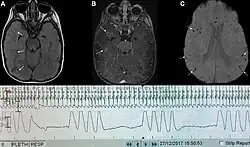

Graph showing ataxic respirations and other pathological breathing patterns.